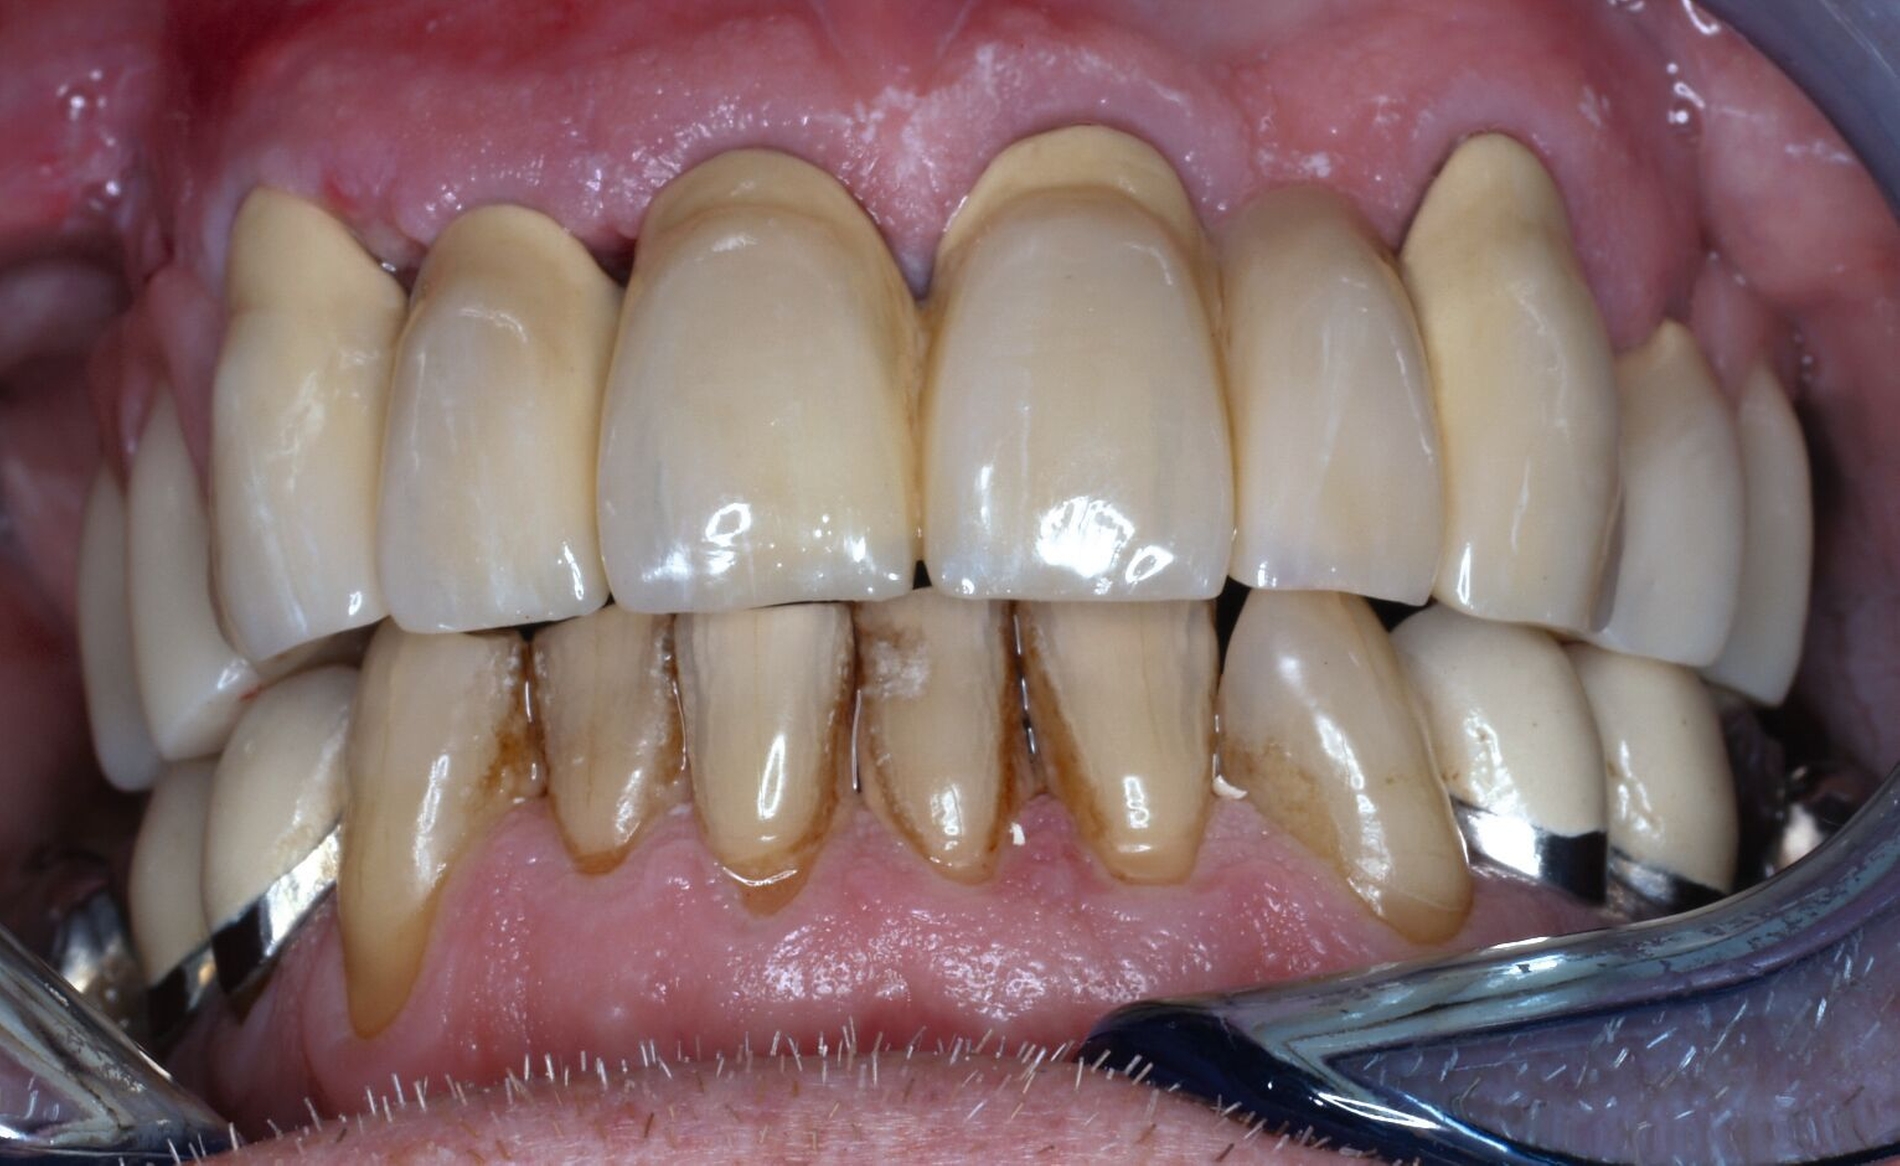

Nachdem die Einheilkäppchen entfernt und die Scanbodies in die Implantate eingeschraubt wurden, erfolgte der Intraoralscan (Abbildung 8c). Der festsitzende Zahnersatz wurde im zahntechnischen Labor designt und aus monolithischem Zirkonoxid gefräst. Die Kronen konnten schließlich selbstadhäsiv auf den Stümpfen befestigt werden. Das Einschrauben der Implantatkronen erfolgte mit Drehmomentschlüssel auf 35 Ncm nach Herstellerangabe. Die Schraubkanäle wurden anschließend verschlossen. Mit dem Endergebnis (Abbildung 8d) zeigte sich der Patient auch im Recallverlauf hochzufrieden.

Um den Sitz der Implantatkronen nach dem Einsetzen zu prüfen, wurden intraorale Tubusaufnahmen im Sinne eines Baseline-Röntgens angefertigt (Abbildung 9). In den Folgeterminen wurde dem Patienten noch eine Aufbissschiene für den Oberkiefer eingegliedert, um etwaigem nächtlichen Bruxismus vorzubeugen. Für die Nachsorge empfiehlt sich ein halbjährliches Kontrollintervall.